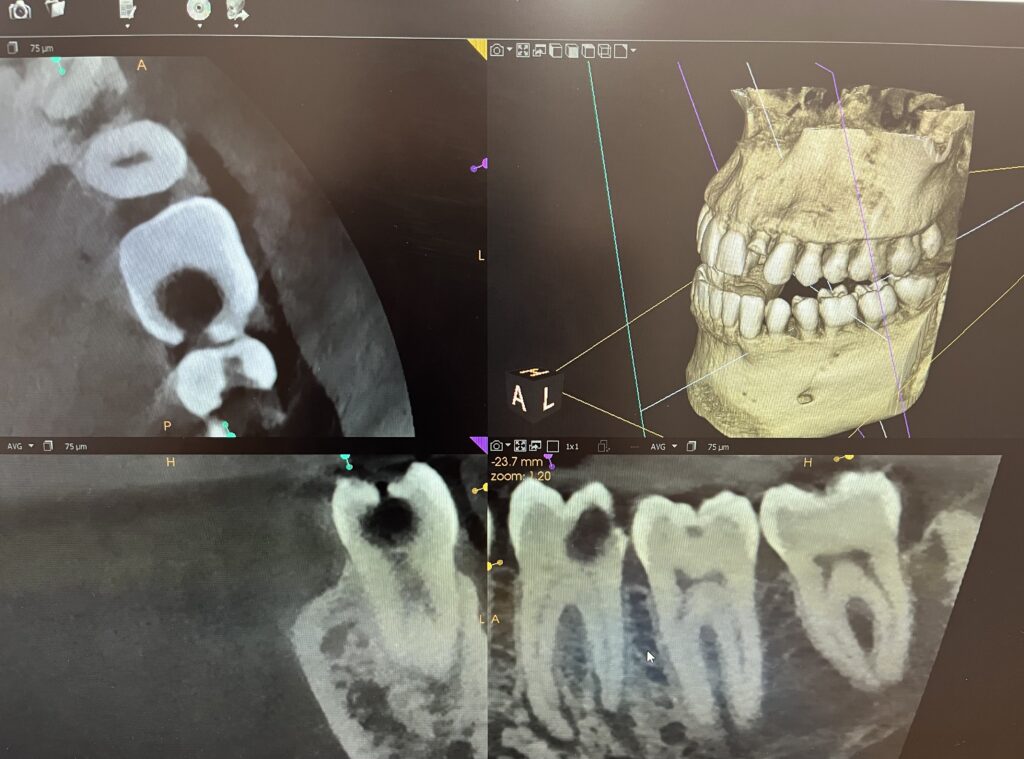

Sacramento Endodontics Imaging and X-Ray of Patient

X-Ray Imaging: Patient Analysis